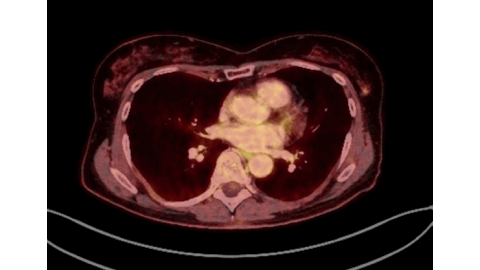

Marked FDG Uptake on PET/CT Corresponding to Low-Grade Ductal Carcinoma In Situ of the Breast: A Case Report - Denmark

https://doi.org/10.59667/sjoranm.v23i1.14

This case demonstrates that a focal isolated area of increased FDG uptake on PET-CT should not be disregarded, even if no corresponding lesion is identified on second-look ultrasound.

Low-grade DCIS (Van Nuys Grade 1) may show FDG activity on PET-CT despite its subtle nature.